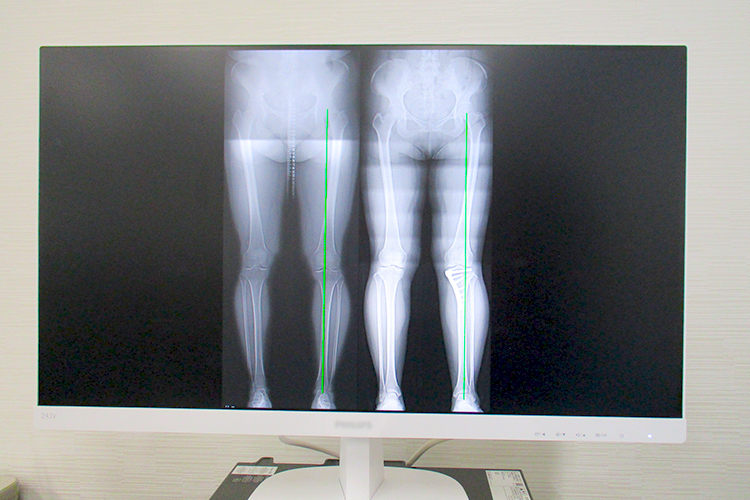

状態をしっかり見極め、適切な治療を継続していく

変形性関節症は、関節の変形によって軟骨がすり減り、痛みやこわばり、可動域の制限を引き起こす病気です。内側型の変形性膝関節症では、O脚変形により膝の内側に過剰な荷重がかかり、走ったりジャンプしたりする動作で痛みが増し、思うようにプレーできなくなることも。また、関節の変形や不安定性が進むと、バランスや動きの安定性が損なわれ、けがのリスクも高まります。軽度の場合はリハビリテーションや筋力強化、関節への負担を減らす装具でスポーツを続けることも可能ですが、中等度以上では症状悪化を防ぐため運動制限や高位脛骨骨切り術などの手術が必要です。入院は3〜4週間、スポーツ復帰や重労働は術後3ヵ月以降が目安です。